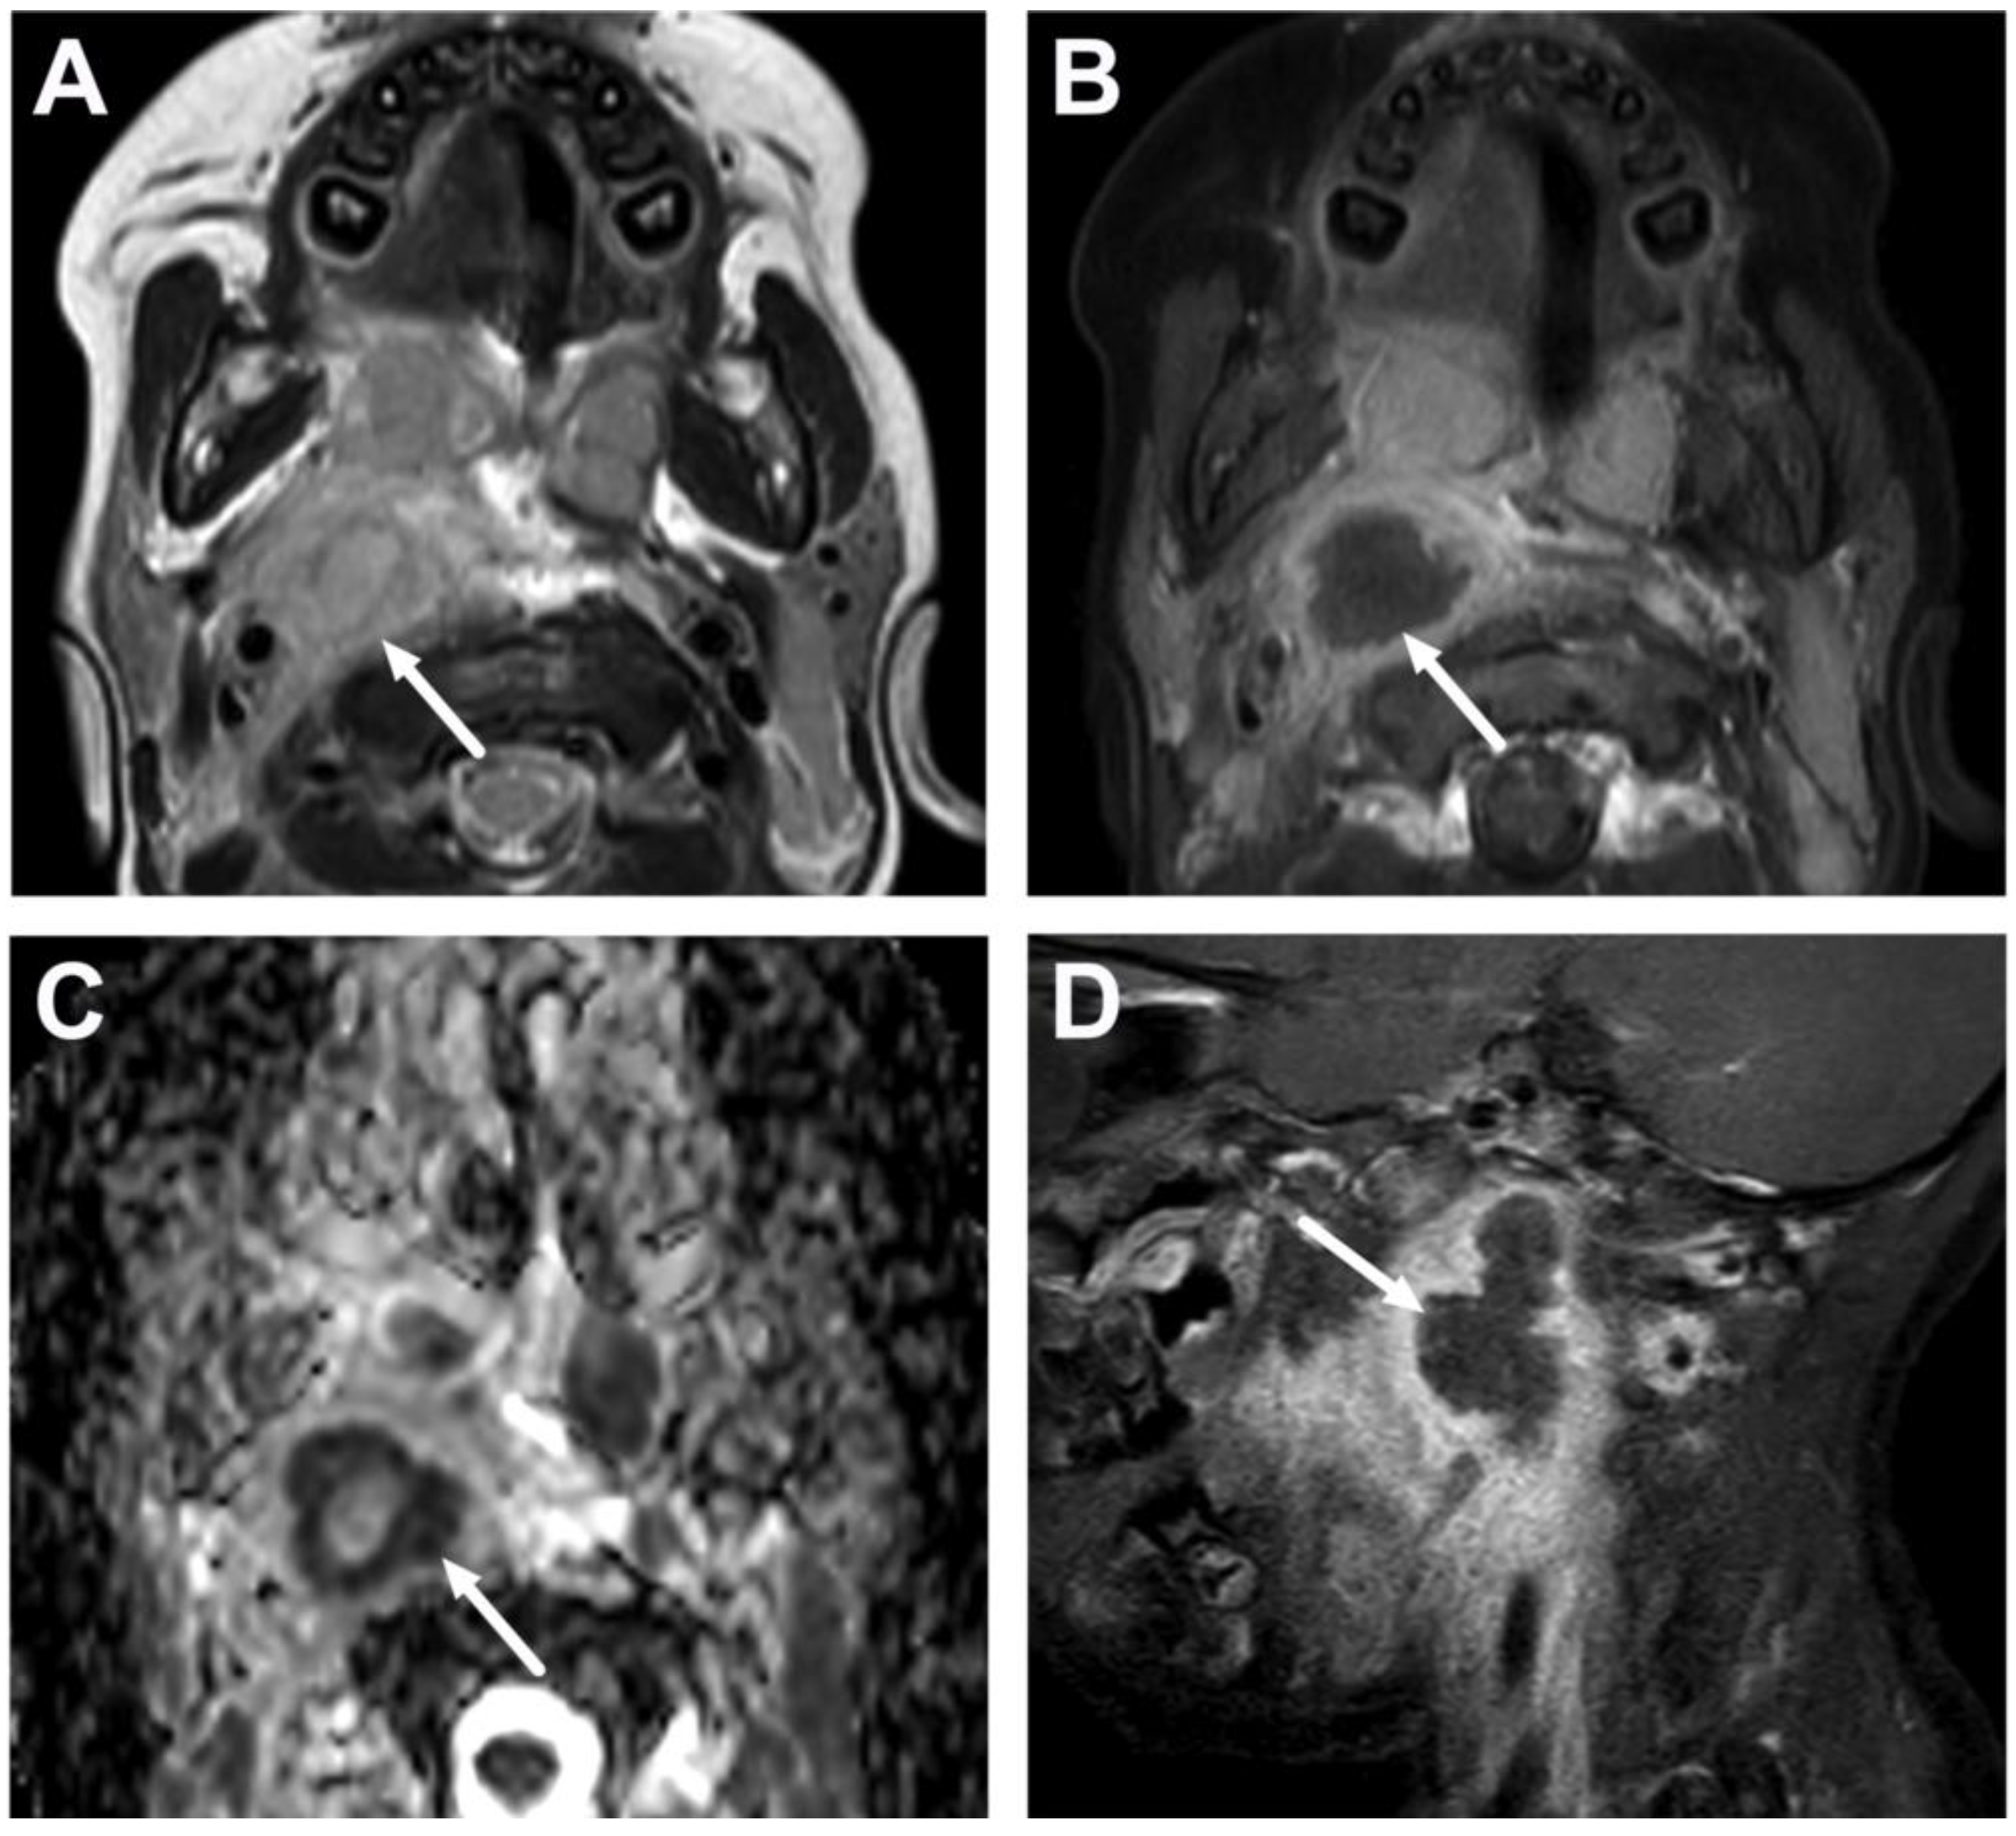

4.3. Oral Cavity

| Abscess | T1 SE T2 Dixon (water) DWI post-contrast T1 Dixon (water) | Non-enhancing collection with low ADC values enclosed in abnormally enhancing soft tissue edema. | Detection of an abscess usually requires operative consideration and exact abscess location, and extensions are useful in operative planning. | Abscesses may have an intermediate T2 signal content; blood products and/or postoperative status may complicate abscess assessment; necrotic lymph nodes may be misinterpreted as suppurative lymphadenitis. |